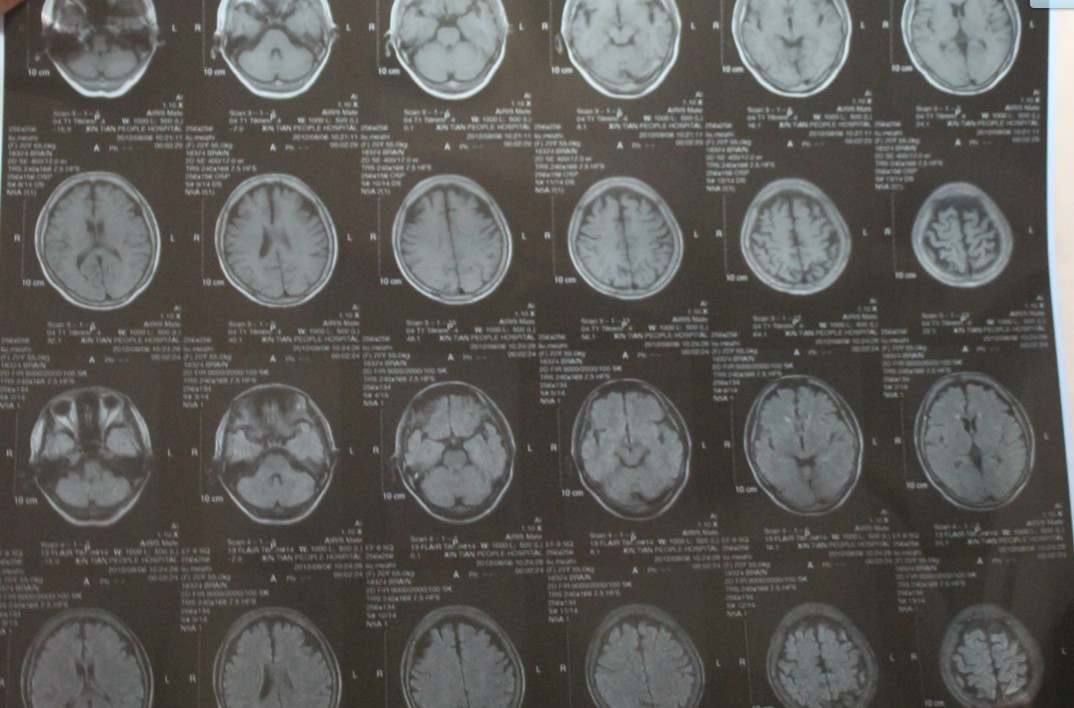

脑萎缩核磁

脑萎缩核磁,

脑萎缩 右侧额叶局限性萎缩(硬膜下间隙增宽 患者,男性,非aids 病程

2019-01-13沈阳儿童医院头ct提示颅内出血基本吸收,左颞顶叶脑萎缩

怎样看脑萎缩的影像

原创ct磁共振报告上的脑萎缩是什么或是3种疾病引起要留心